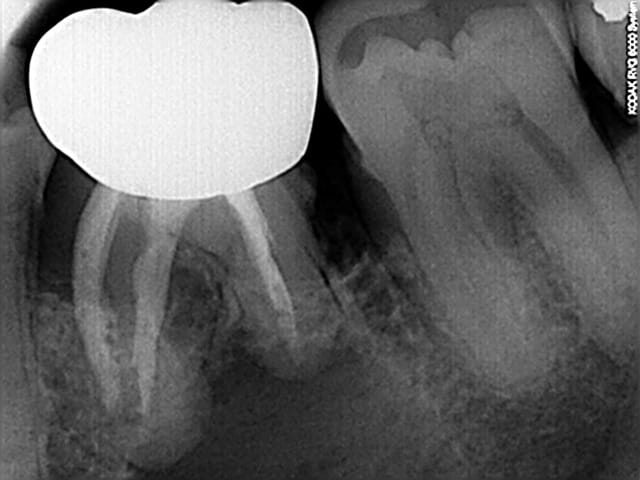

voila la retro,je reprends l'endo (faite en 1982) avec les techniques 2008, j'ai expliqué la possibilité de continuer chez l'endodontiste et celle d'etre amené a extraire....

Le panoramique dentaire, ou clichés rétro-alvéolaires, montre une ostéite

radiotransparente localisée autour de l’apex et appelée granulome ou kyste

apical en fonction de la taille (Fig. 4a, 4b).